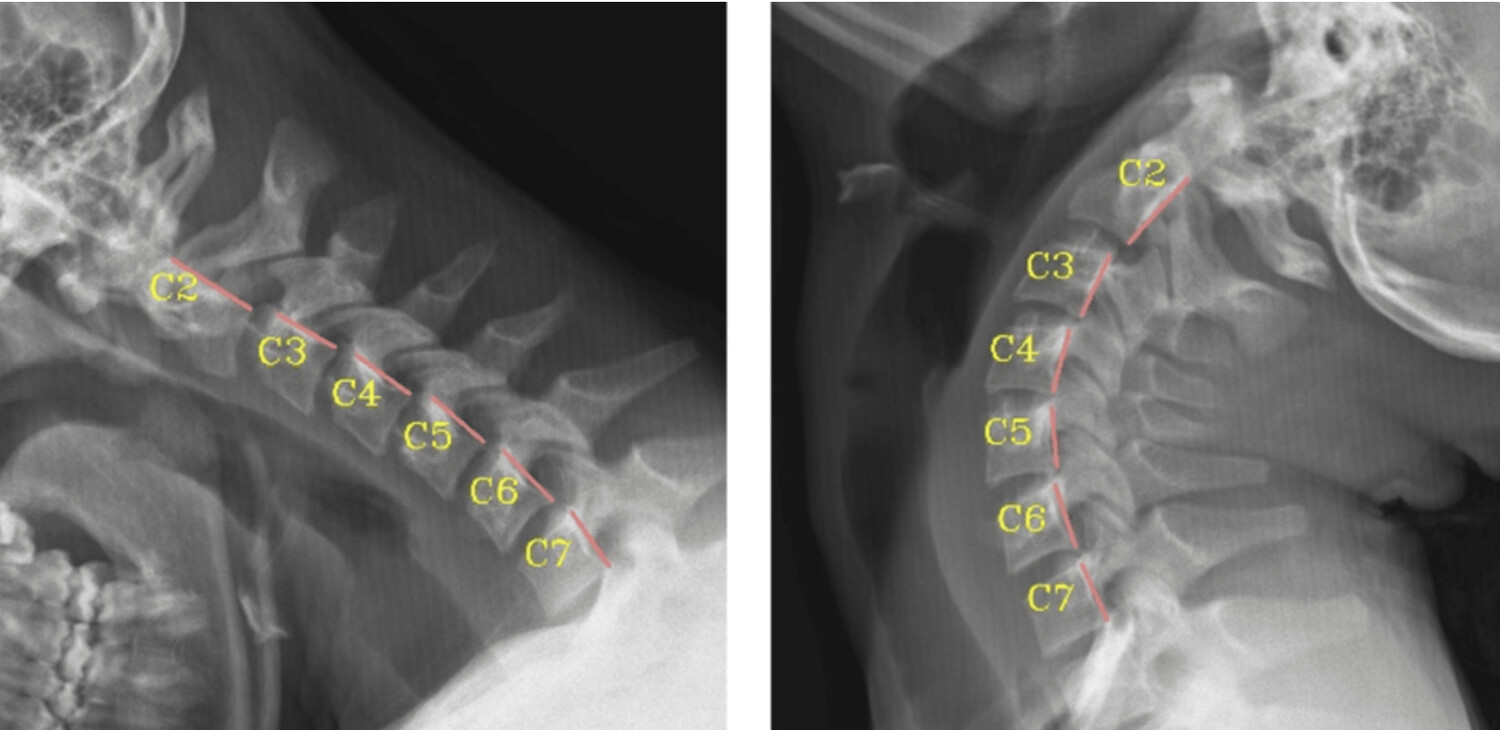

A recen peer-reviewed publication in a medical journal, a retrospective cross-sectional analysis of 37 adolescents and young adults with scoliosis to evaluate cervical spine biomechanics, finding that 100% of participants exhibited cervical instability and loss of normal lordosis, most often manifesting as increased translational motion (instability) particularly at the C3-C4 and C5-C6 segments, and pervasive cervical buckling patterns even when measured angular deviations were infrequent; these findings demonstrate a consistent association between abnormal cervical mechanics and adolescent idiopathic scoliosis, expanding the understanding of spinal biomechanics beyond the scoliotic curvature itself and suggesting that the cervical spine may play a substantive role in the complex biomechanical profile of scoliosis, warranting further longitudinal and etiological investigation.

A Retrospective Cross-Sectional Analysis of Abnormal Cervical Mechanics in Patients With Scoliosis

This retrospective cross-sectional study analyzed radiographic data from 37 adolescent idiopathic scoliosis patients to characterize abnormal cervical mechanics, finding a high prevalence of cervical instability, loss of normal lordosis, and buckling patterns that correlate with scoliosis biomechanics.